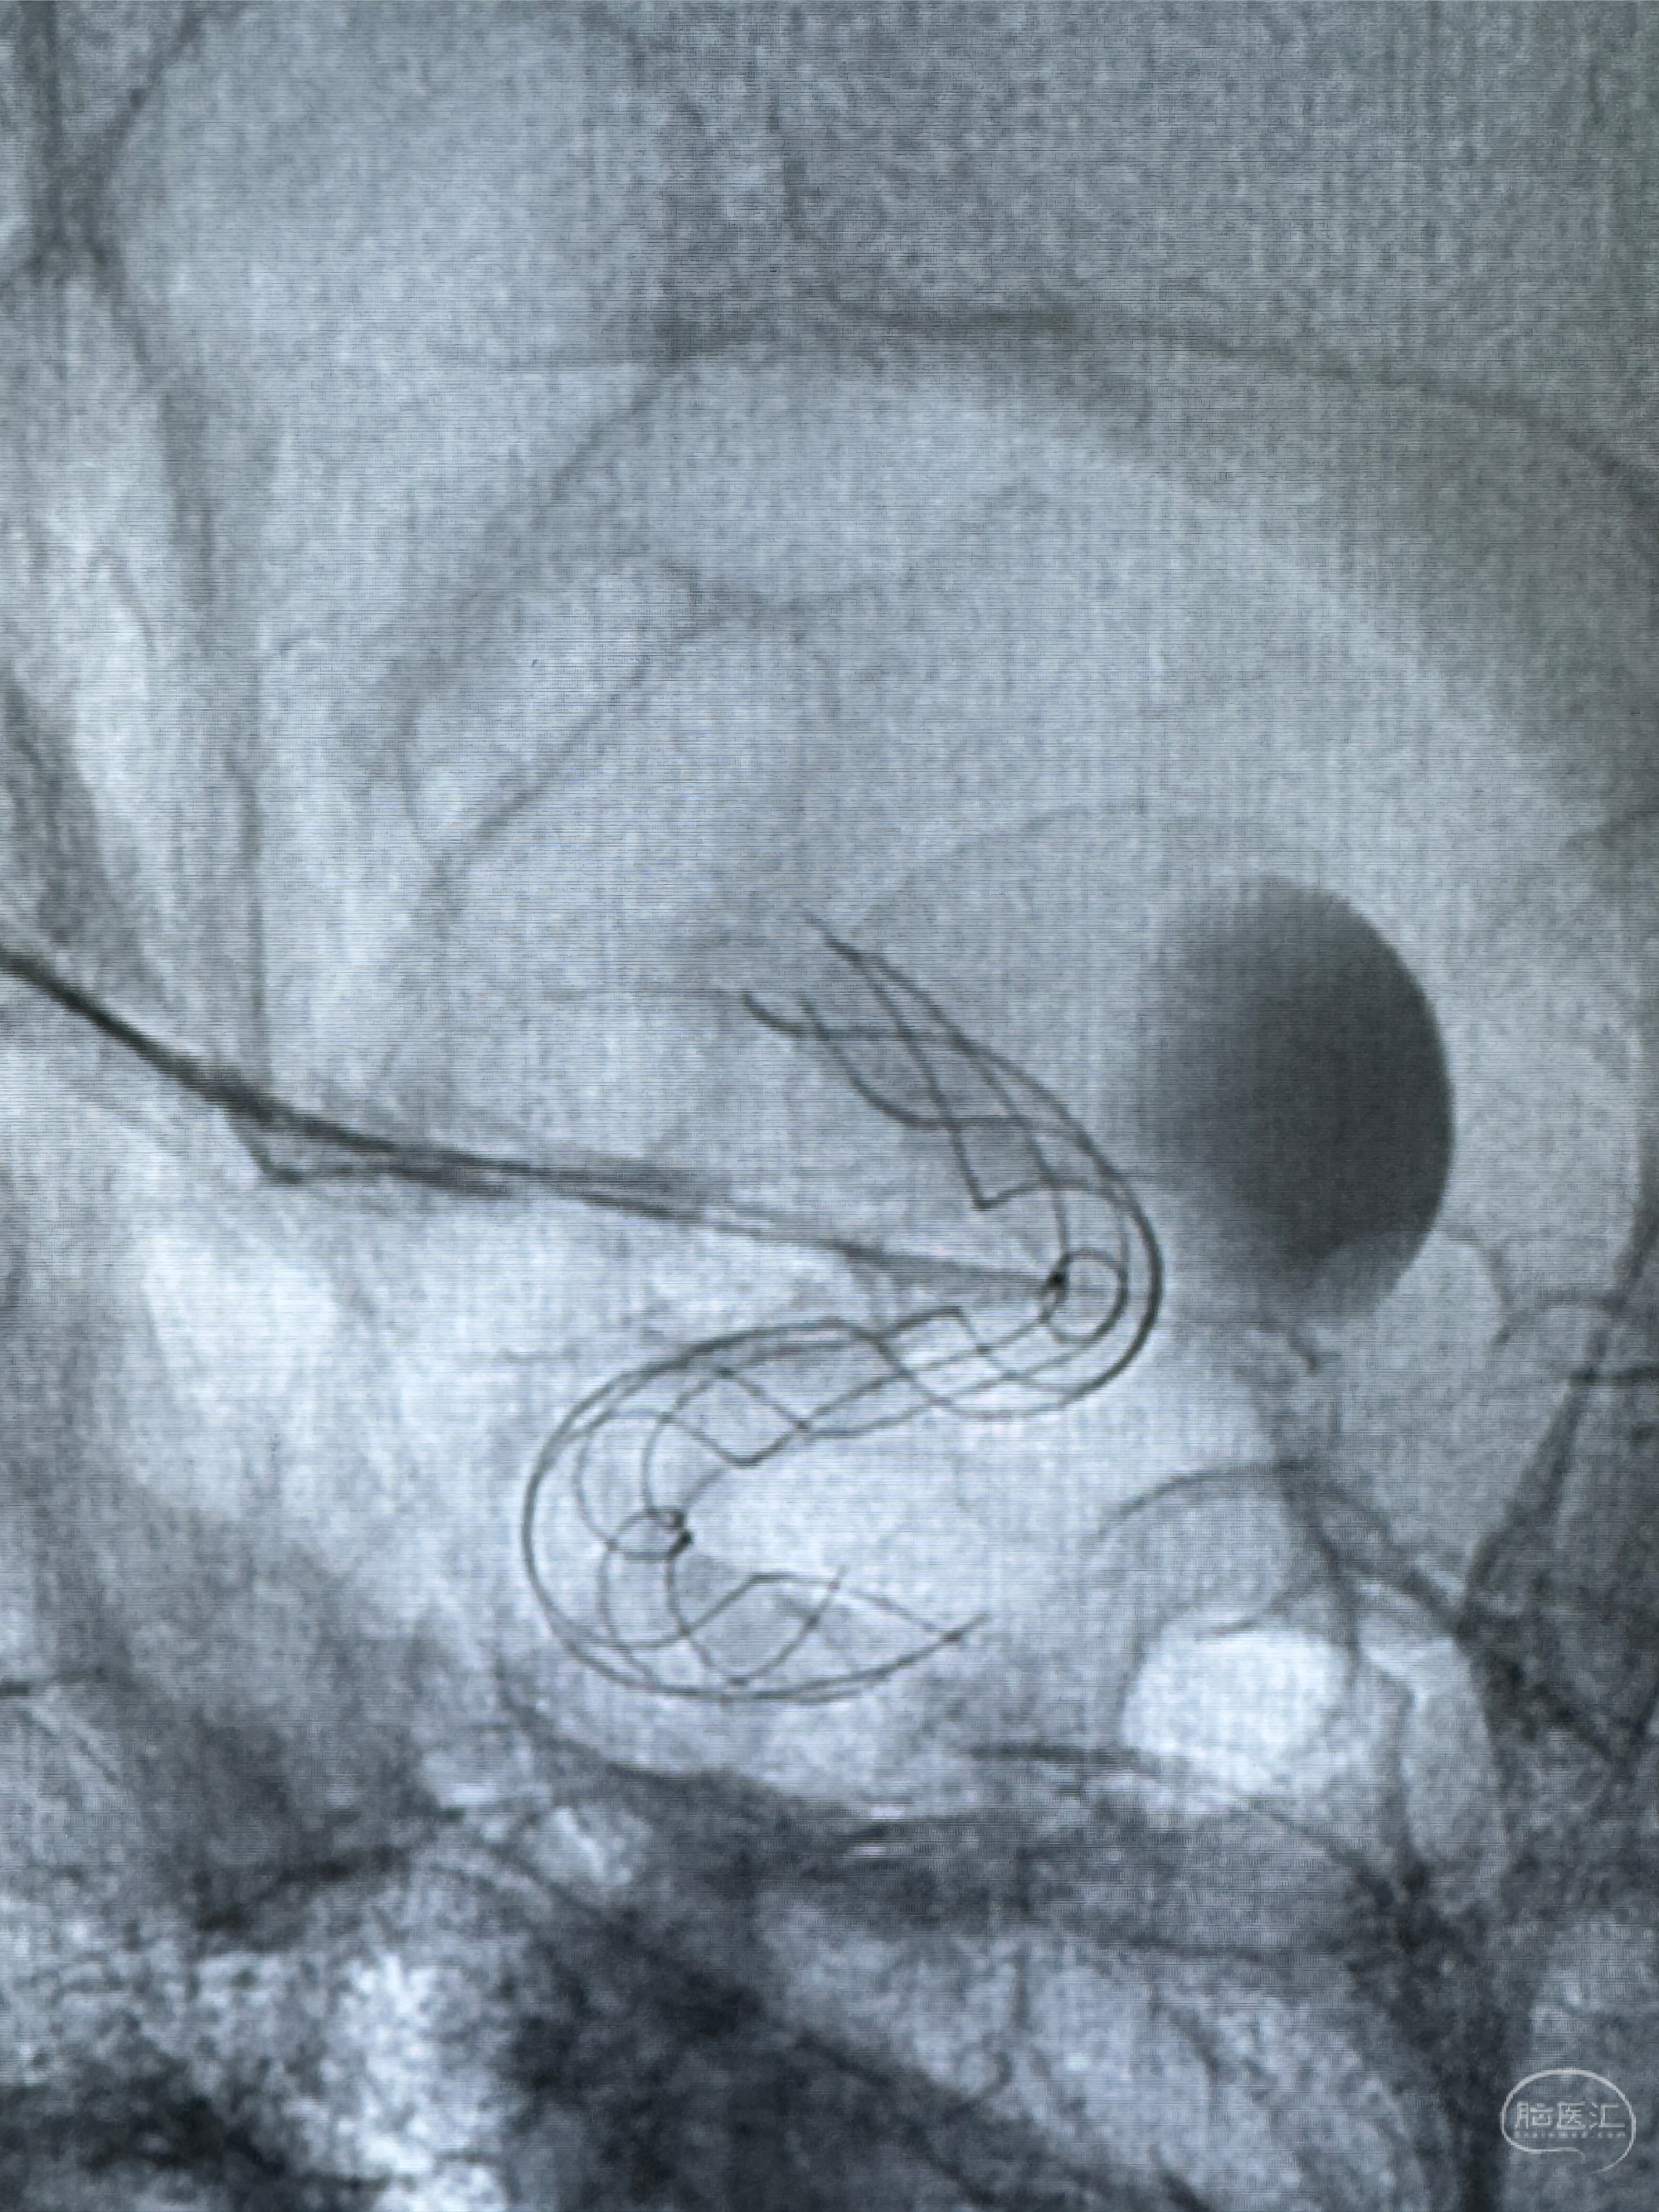

4.5-30mmTurbridge密网支架,于M1近心端打开

透视下支架释放满意

多角度显示支架打开情况

造影显示支架贴壁情况

支架植入顺利,贴壁佳,支架内血流通畅,动脉瘤内血液滞留明显